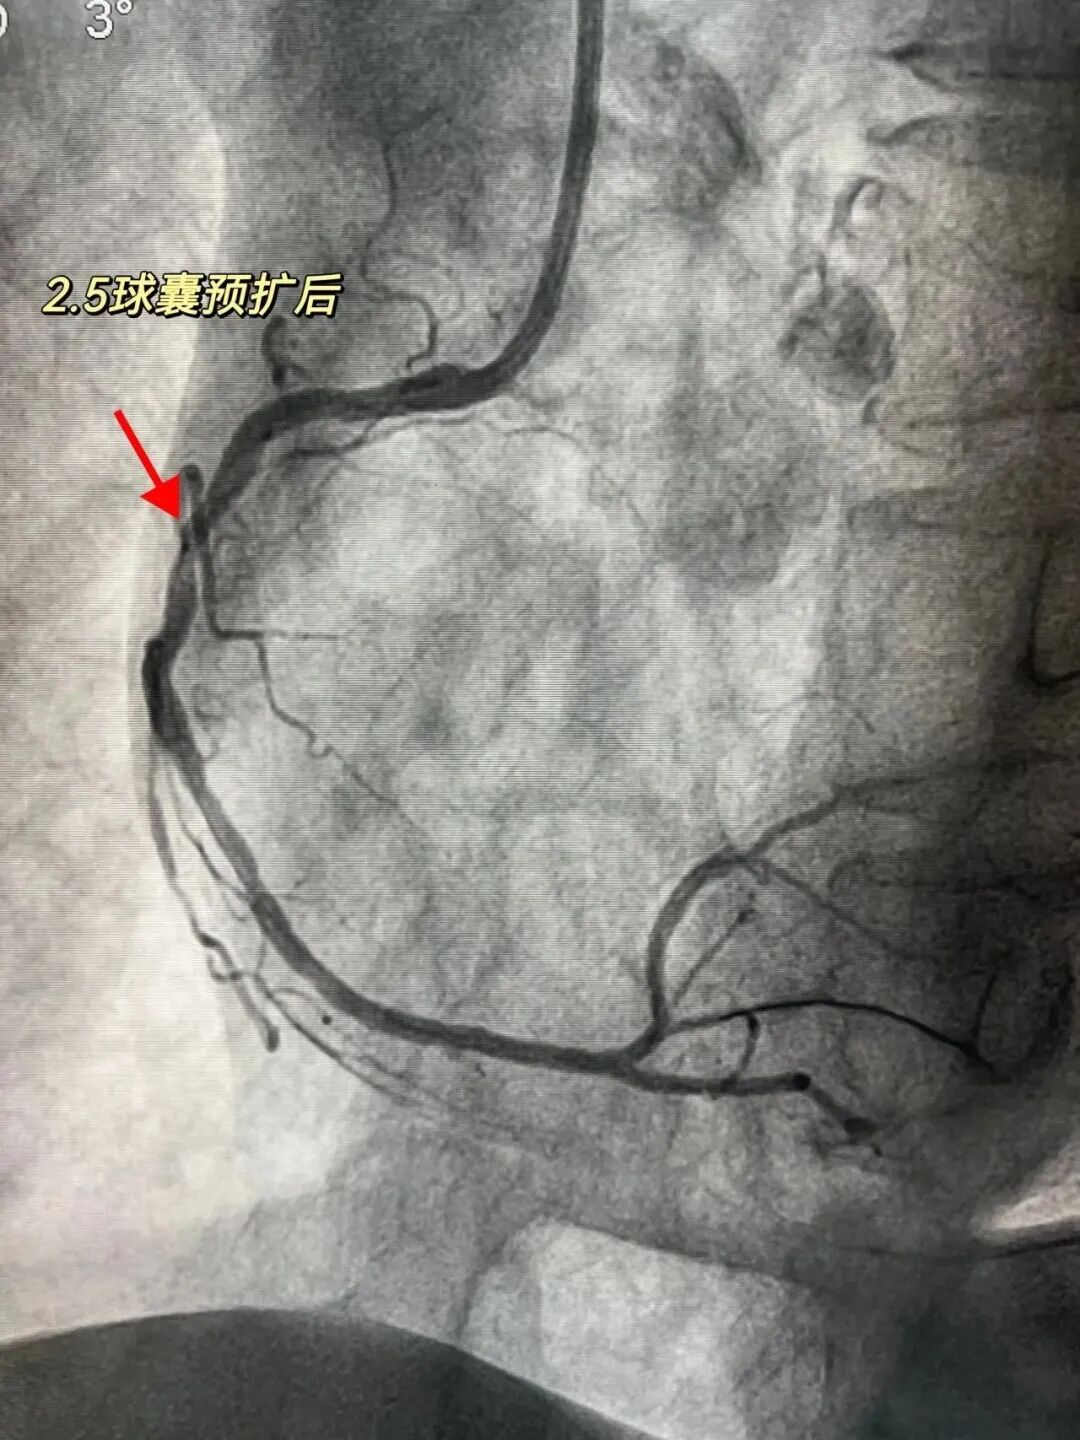

为进一步评估冠状动脉病变程度,入院后心内科团队立即予其行冠脉造影检查,结果提示三支病变,即右冠状动脉、左冠状动脉前降支、左冠状动脉回旋支都已产生“问题”,其中右冠脉近中段钙化严重,最重部位狭窄程度已达到90%-95%。

医院心内科介入团队先常规予工作球囊进行预扩张,然而无法达到理想效果,为查明原因,立即为患者进行IVUS(血管内超声)检查,IVUS能从血管内逐层观察血管病变情况,精准了解血管狭窄程度,对钙化病变的诊断也有很高的敏感性。检查发现右冠脉病变处已存在360°环形钙化。

“因存在环形钙化,球囊扩张时压力聚集,可能导致球囊破裂,造成冠脉夹层、穿孔、破裂、无复流等风险。”经与患者家属充分沟通后,黄主任决定采用Shockwave球囊对钙化病变进行预处理。

“震波球囊就位,释放脉冲!”术中,心内科团队将3.0*12mm Shockwave球囊导管顺利送至钙化病变处,在钙化最严重处进行4组血管内冲击波治疗。治疗后复查IVUS,提示钙化被震裂打开,裂痕明显,钙化狭窄处直径明显增大,这代表原来“石头”似的钙化斑块有些被“震”断了,心内科团队成功运用这种新方法打开患者血管的“紧箍咒”。